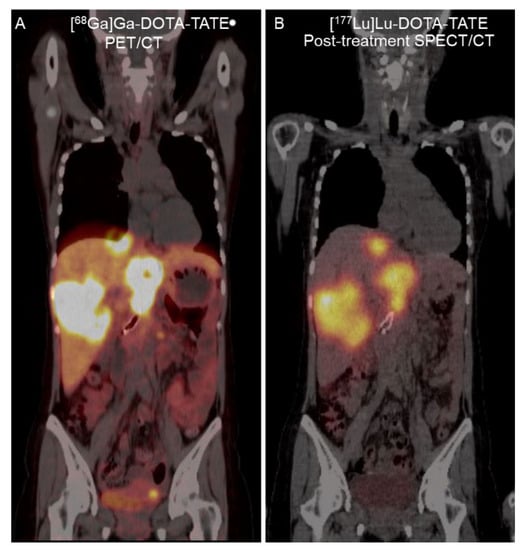

A 32-year-old woman with metastatic pancreatic NET (grade II, Ki-67 of 10%) presented with abdominal pain. She had undergone surgery of the pancreatic tail 5 years previously and received targeted therapy with everolimus, sunitinib, lanreotide, and temozolomide for 2 years. [68Ga]Ga-DOTA-TATE PET/CT revealed multiple SSTR-positive lesions in the bilateral hepatic lobes and intra-abdominal lymph nodes (Figure 3). Thus, she was referred to the Nuclear Medicine Department for PRRT. Four cycles of [177Lu]Lu-DOTA-TATE (7400 MBq per cycle) separated by 8-week intervals were proposed. Her baseline serum creatinine level was 0.43 mg/dL (reference range, 0.50–1.00 mg/dL), and her eGFR (CKD-EPI) was 135.01 mL/min/1.73 m2.

Figure 3. A 32-year-old woman with metastatic pancreatic NET. (A) Coronal fused [68Ga]Ga-DOTA-TATE PET/CT image revealed SSTR-positive liver metastasis. (B) Twenty-four-hour [177Lu]Lu-DOTA-TATE post-treatment fused single-photon emission computed tomography (SPECT)/CT image revealed similar [177Lu]Lu-DOTA-TATE uptake in the liver metastasis.